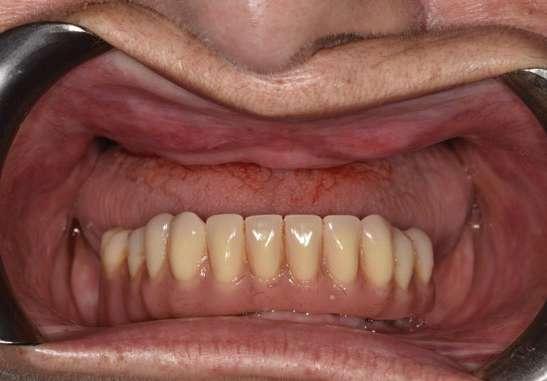

El tiempo de seguimiento fue de 112 meses +/14,85, no observándose ningún fracaso de los implantes estudiados durante este periodo. La media de la pérdida ósea mesial de los implantes estudiados fue de 0,15 mm +/- 0,71 , mientras que la distal fue de 0,31 mm +/- 0,69. Si estudiamos la pérdida ósea crestal separada entre los implantes atornillados y cementados obtenemos que para los implantes cementados la pérdida ósea distal fue de 0,47 mm +/- 0,80 y para los atornillados de 0,15 +/- 0,59 mm siendo las diferencias entre ambos grupos para la pérdida ósea distal estadísticamente significativas (p=0,03). En cambio, para la pérdida ósea mesial, no existieron diferencias estadísticamente significativas para los implantes atornillados y cementados, siendo la media de la pérdida ósea para los cementados de 0,27 +/- 0,83 y para los atornillados de 0,10 +/- 0,60. En la pérdida ósea de conjunto (media de la mesial y distal) para los grupos atornillado y cementado no existieron tampoco diferencias óseas significativas. En las figuras 3-10 se muestran imágenes de dos de los casos incluidos en el estudio.

Figuras 3-6. Imágenes de un caso de prótesis atornillada en molar unitario inferior. Vemos el estado de los tejidos blandos gingivales tras la segunda fase y colocación del transepitelial unitario y la radiografía. En las imágenes inferiores (5 y 6) observamos el caso a los 4 años y 10 años de seguimiento, con estabilidad completa de los tejidos óseos peri-implantarios.

Figuras 7-10. En las dos imágenes superiores (7 y 8) observamos la realización de la prótesis cementada mediante un bioplilar fresado a la altura gingival con la radiografía antes del cementado de la corona. En las imágenes inferiores (9 y 10) vemos la prótesis a los 7 años de seguimiento y a los 9 años transformada en una prótesis atornillada al perderse la pieza anterior al implante y realizarse un puente con el nuevo implante. En este caso, el nivel óseo permanece estable con el paso del tiempo.